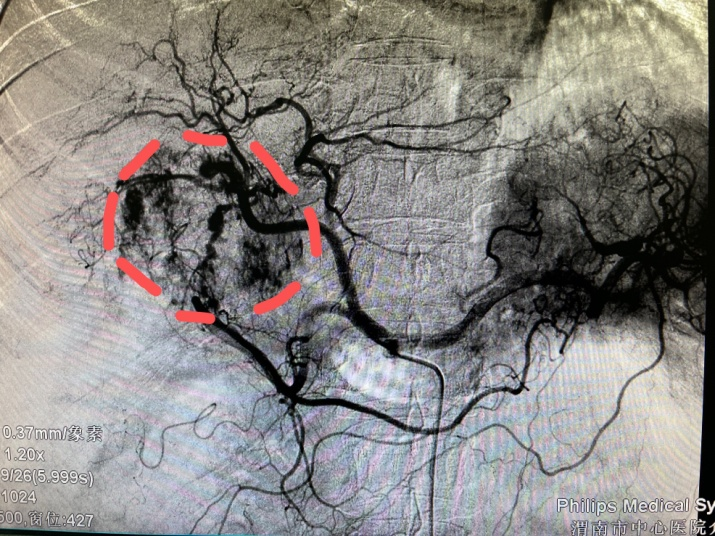

患者女性,57岁,3月12日,突发腹部疼痛就诊于当地医院,CT示肝肿瘤破裂出血,随即转入市中心医院急诊科,分诊后入住普外科二病区。急查实验室检查示:血红蛋白71g/L,血压85/60mmHg左右,正值周日,值班人员电话紧急请介入科会诊,经分析,患者随时有失血性休克风险,当即立断启动疫情状态下的急危重症患者介入诊疗绿色通道。应急值班人员第一时间到位,行肝动脉造影明确了出血动脉(部位),现场评估并制定了手术方案,对肿瘤出血进行了封堵及TACE,术后给予止血、保肝、输血、抗感染等对症处理,病情稳步好转。复查CT肝内碘油沉积良好(提示介入治疗疗效佳),目前已安全出院。